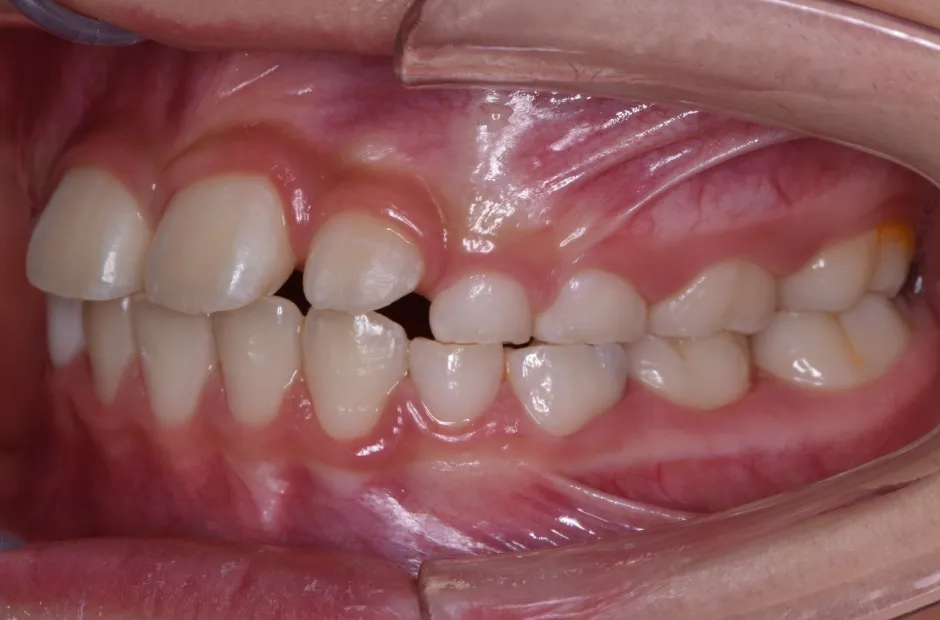

治療症例

ブラケット矯正

前歯部反対咬合

| 診断名・主訴 | 前歯部反対咬合 |

|---|---|

| 年齢・性別 | 14歳・男性 |

| 治療期間・回数 | 1年2か月 |

| 治療に用いた主な装置 | ブラケット矯正 |

| 抜歯部位 | なし |

| 治療費 | 60万円(税抜) |

| リスク・副作用 | 装置による違和感・疼痛・歯肉退縮・歯根吸収・虫歯のリスクなど |

治療前